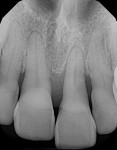

Clinical evaluation revealed that tooth No. 9 was extruded and facially positioned. Probing depths measured between 2 mm and 3 mm, with up to 7 mm of recession and no attached keratinized tissue. The tooth demonstrated Miller class 3 mobility with detectable fremitus. Radiographically, severe bone loss was noted near the tooth and only a few millimeters of bone was present from the apex of the tooth to the nasal floor (Figure 2). The adjacent teeth presented with probing depths measuring 2 mm to 3 mm, recession up to 4 mm, and Miller class 1 mobility. Although the patient had a low smile line,8 she was unhappy with the marginal gingival discrepancy between her central incisors.